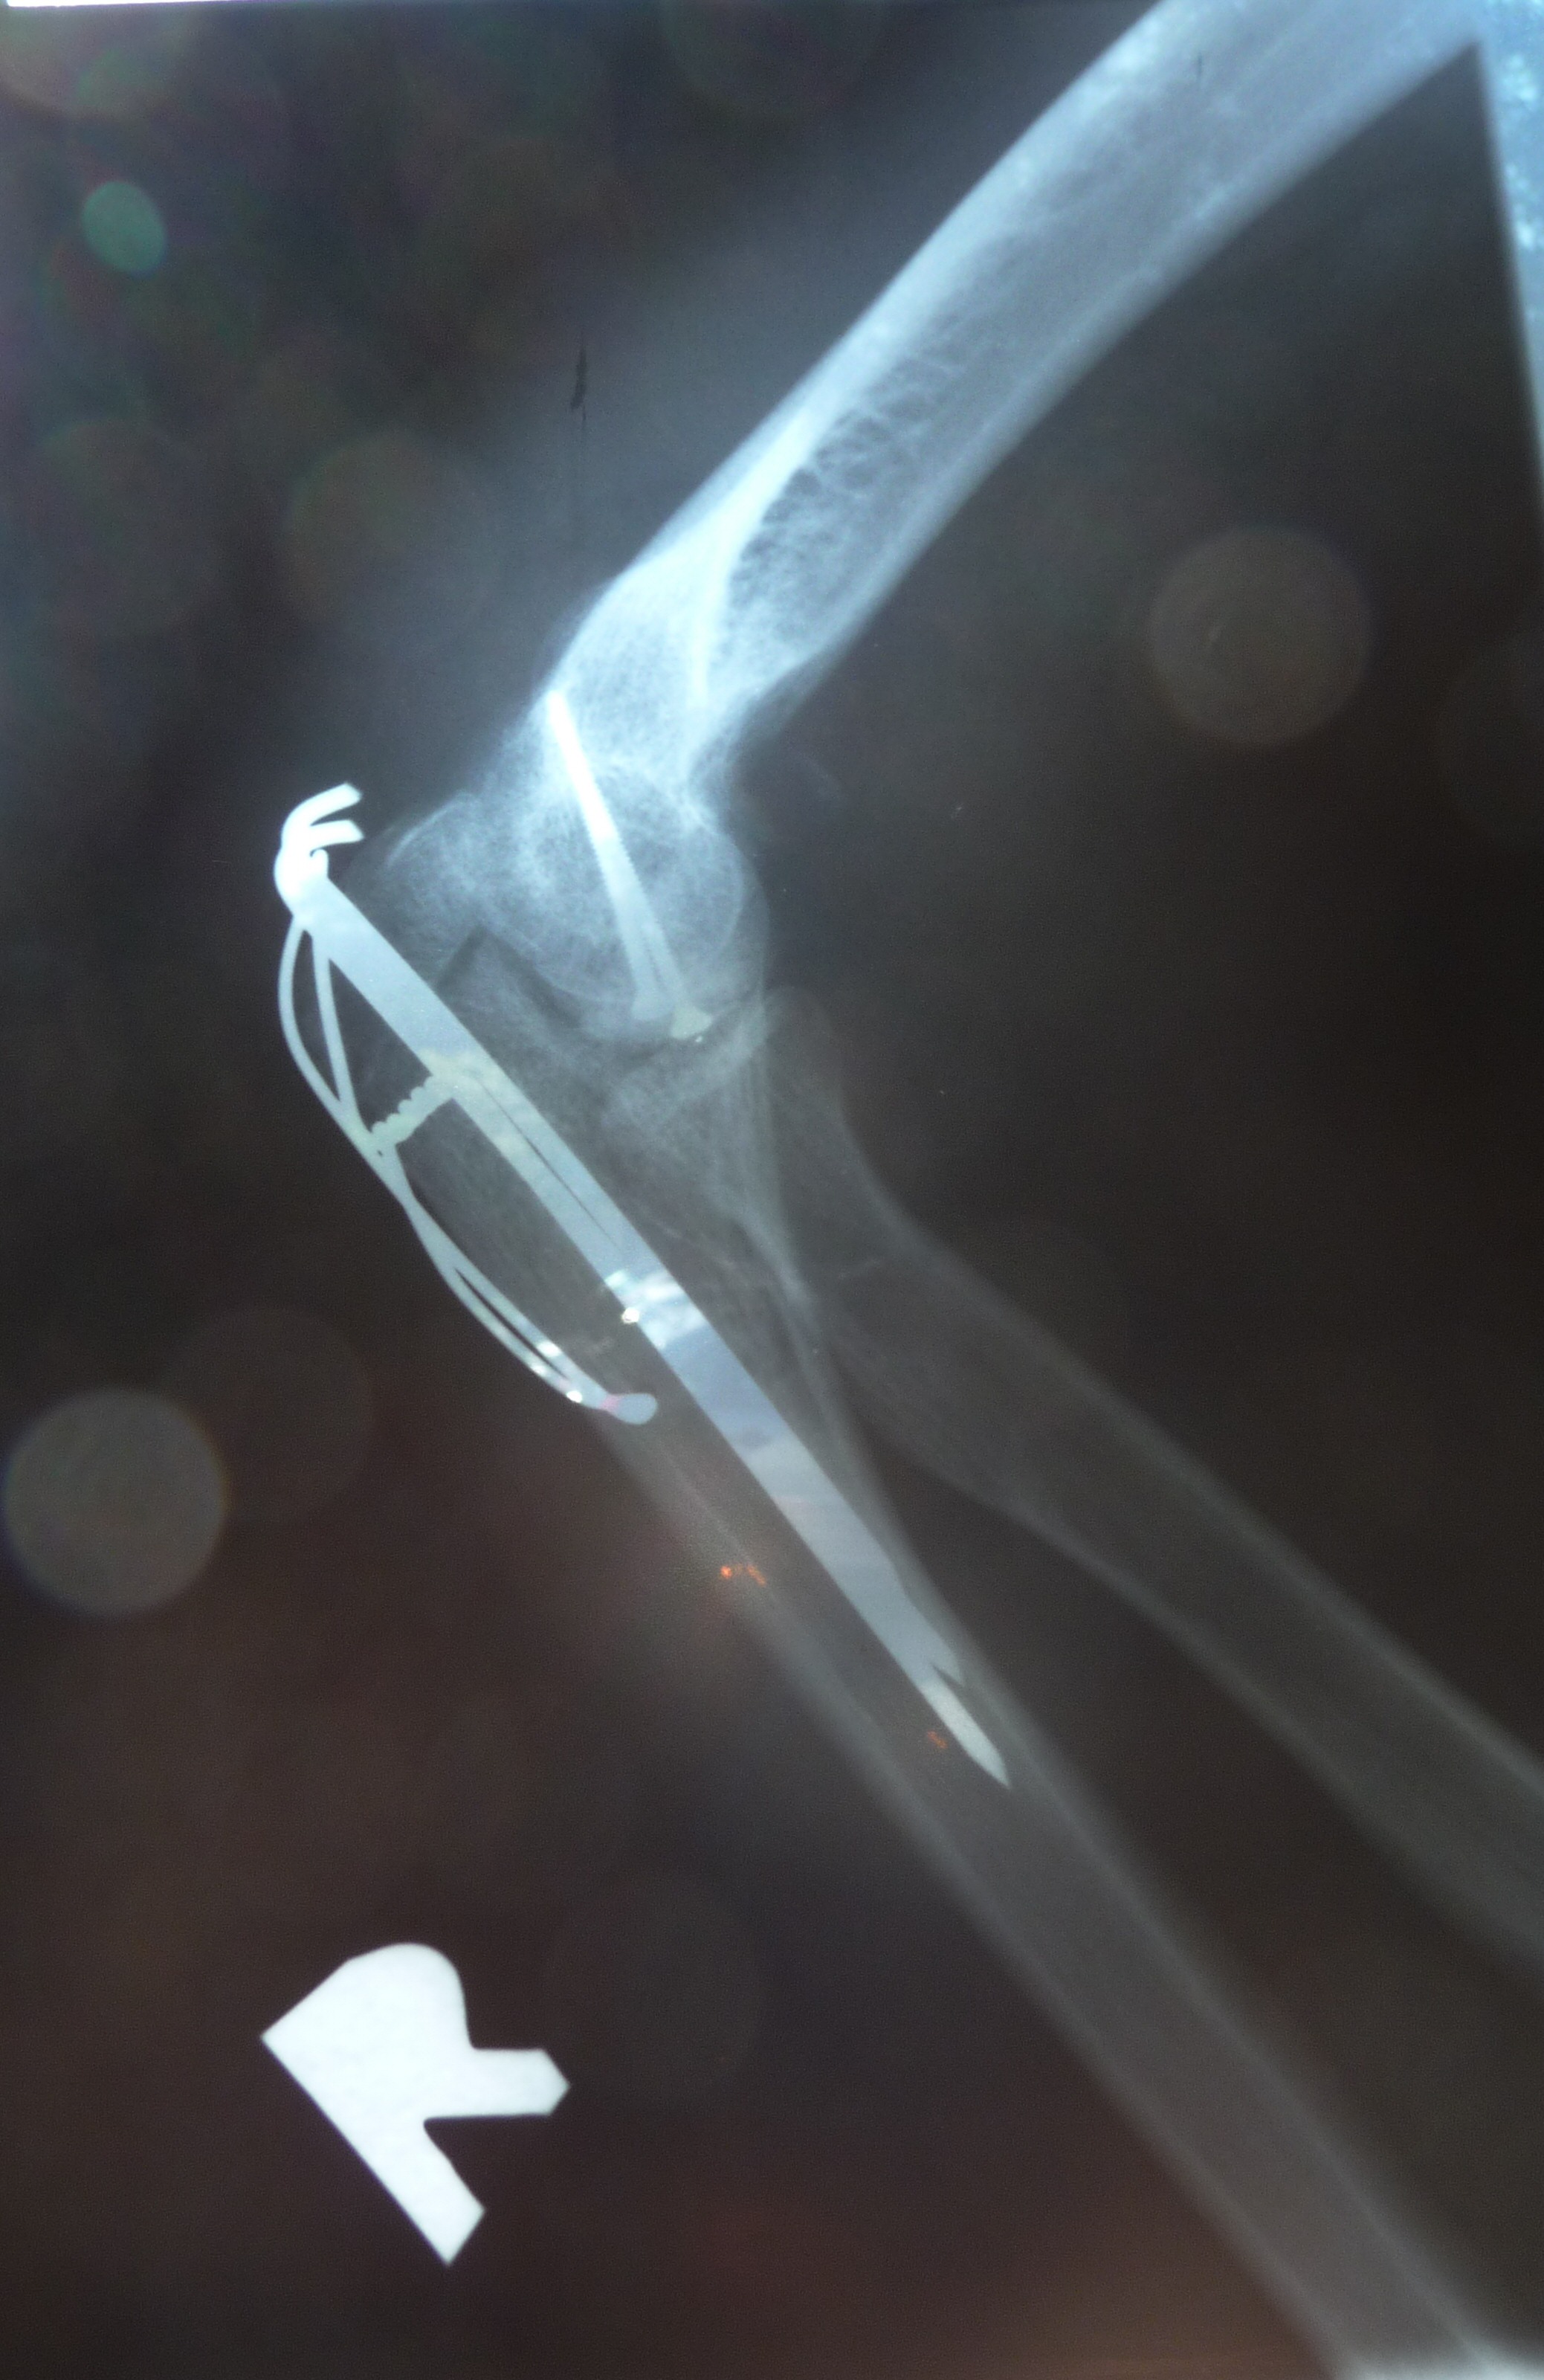

[IMG]rg2_x.jpg2009-09-05 22:28 937K